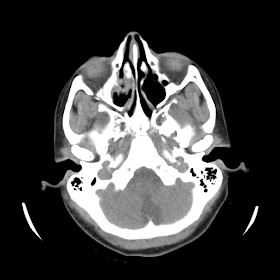

A 33 years old woman with protruding eyeballs & hyperthyroidism since 2 years